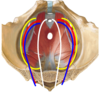

Neurovascular organization of the pelvis:

- NVA runs within endopelvic fascia.

- Arranged in concentric layers, lateral to medial: SVA

- somatic nerves (lateral)

- blood vessels

- autonomic nerves (medial)

Label all:

- NVA of pelvis; lateral to medial: SVA

- somatic nerves (yellow)

- blood vessels (blue/red)

- autonomic nerves (white)